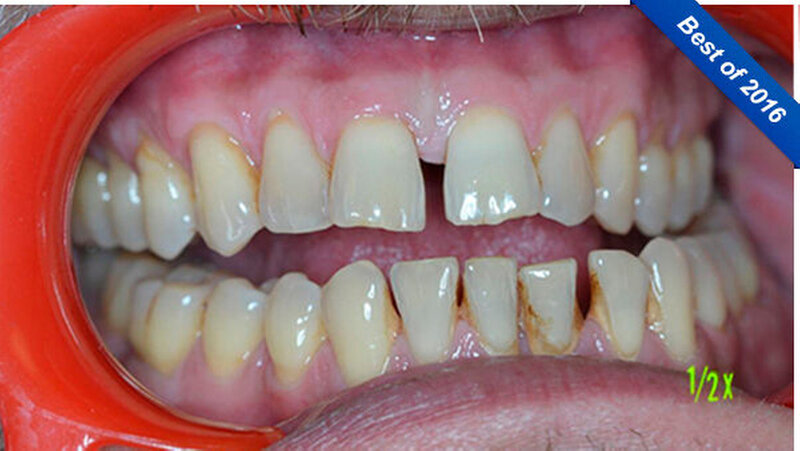

Ein 51-jähriger sportlich muskulöser Patient mit kariesfreiem Gebiss stellte sich zur konsiliarischen Untersuchung vor einer Operation der Kieferhöhle vor. Auf dem OPT imponieren der im Oberkiefer deutlich erkennbare horizontale Höhenverlust mit starker vertikaler Komponente in Regio 15/16 sowie der im Unterkiefer starke vertikale Knochenverlust in Regio 36. Allgemeinerkrankungen oder Medikationen wurden anamnestisch verneint.